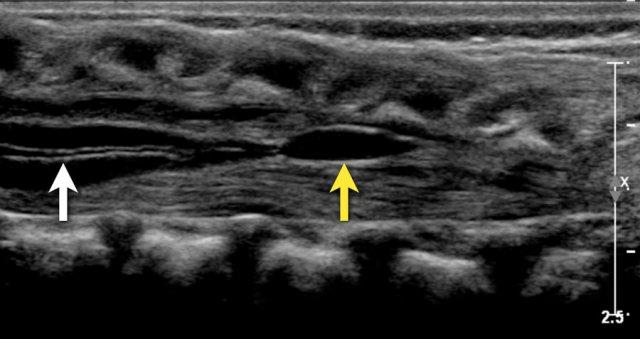

Bé gái 2 tuần tuổi có lỗ rò vùng cùng. Có hình ảnh rỗng tủy nhẹ (mũi tên trắng) và nang trong filum terminale (mũi tên vàng), cả hai đều là biến thể bình thường.

Ống trung tâm

Trong hình ảnh này, ống trung tâm hiện diện như một đường vô âm mảnh trong tủy sống (mũi tên trắng).

Mặc dù đôi khi liên quan đến bệnh lý, đây thường là phát hiện bình thường.